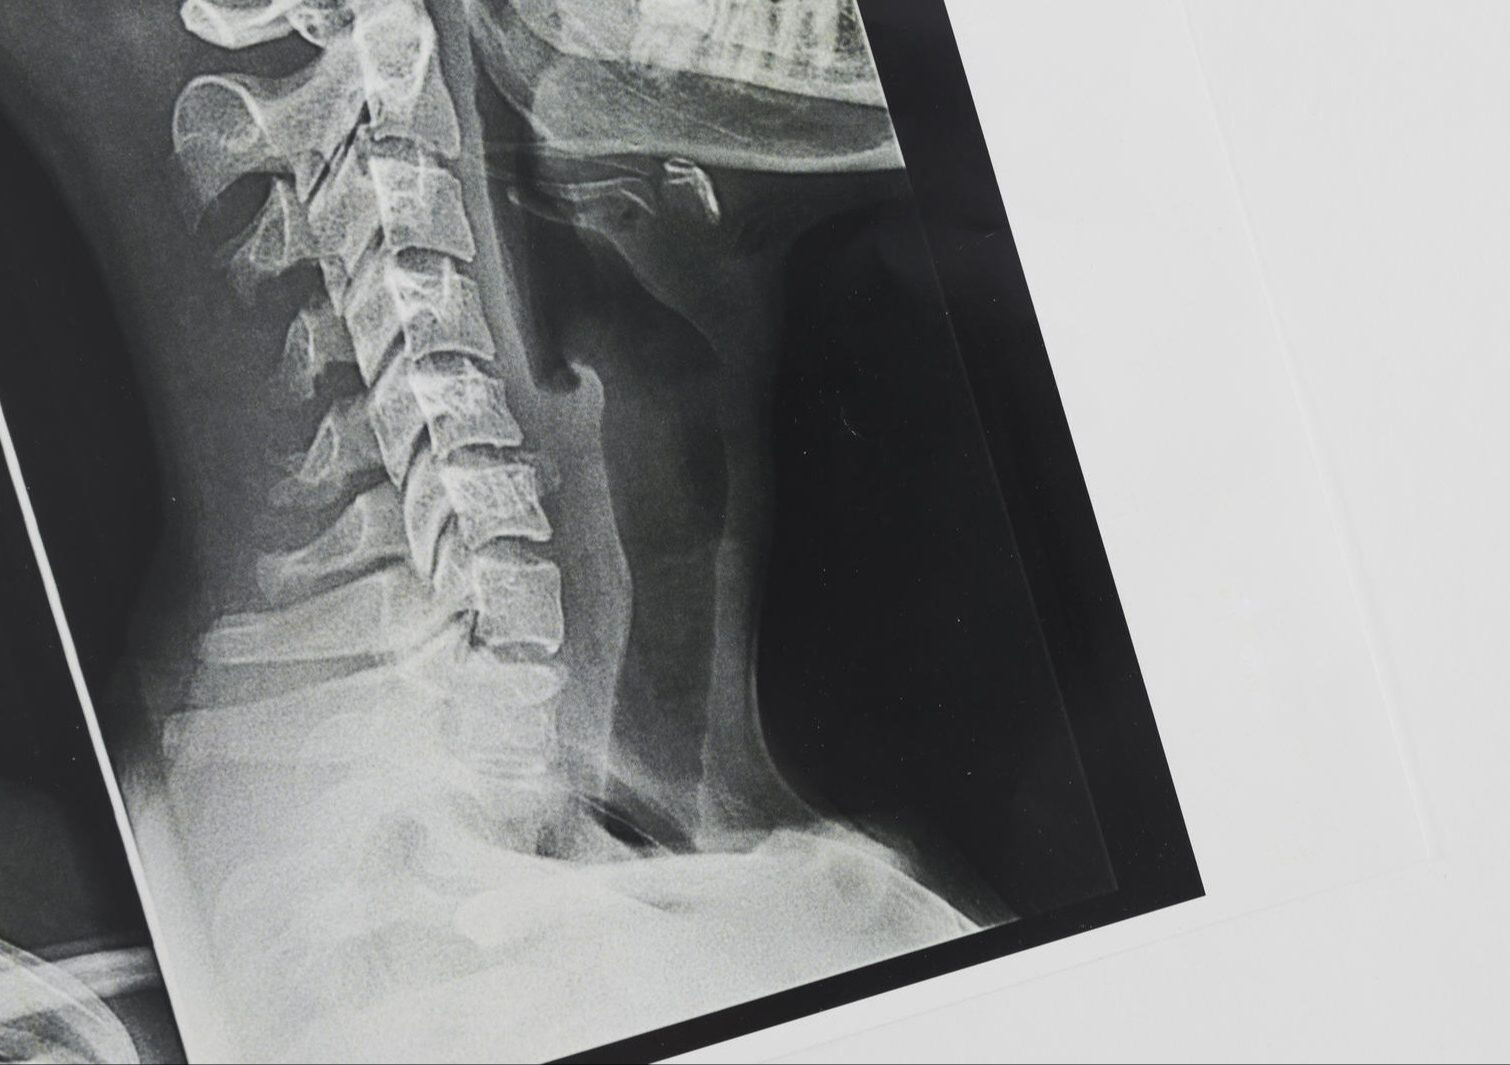

BOYUN DÜZLEŞMESİ NEDİR?

Boyun düzleşmesi tıbbi adıyla servikal lordoz kaybı boyun omurlarındaki doğal eğriliğin kaybolması durumudur. İnsan omurgası; boyun, sırt, bel ve kuyruk sokumu bölgelerinde doğal kavislerle dengelenmiş bir yapıya sahiptir.

Boyun bölgesinde olması gereken içe doğru eğri düzleştiğinde, omurgaya binen yük artar. Bu da zamanla kaslarda spazm, bağ dokuda zorlanma ve sinirlerde baskıya neden olabilir.